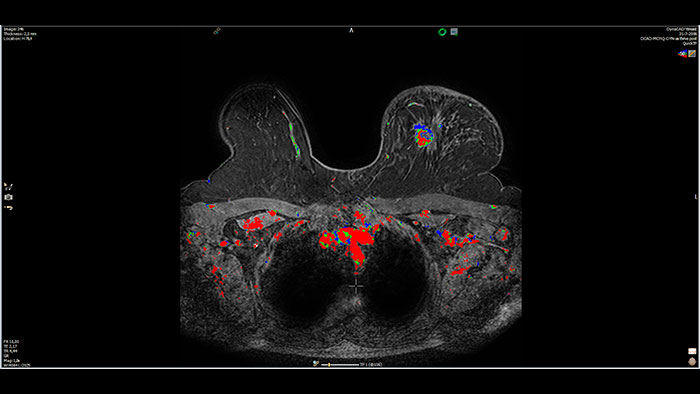

Next generation of breast care

Tailored to enhance the review and analysis of MRI breast studies by providing a flexible workspace with custom hanging protocols and multi-vendor** viewing capabilities. DynaCAD’s automatic segmentation allows on-the-fly user modification and provides volume analysis, lesion composition statistics, histograms, and a 3D rendered morphological overview.

Benefits